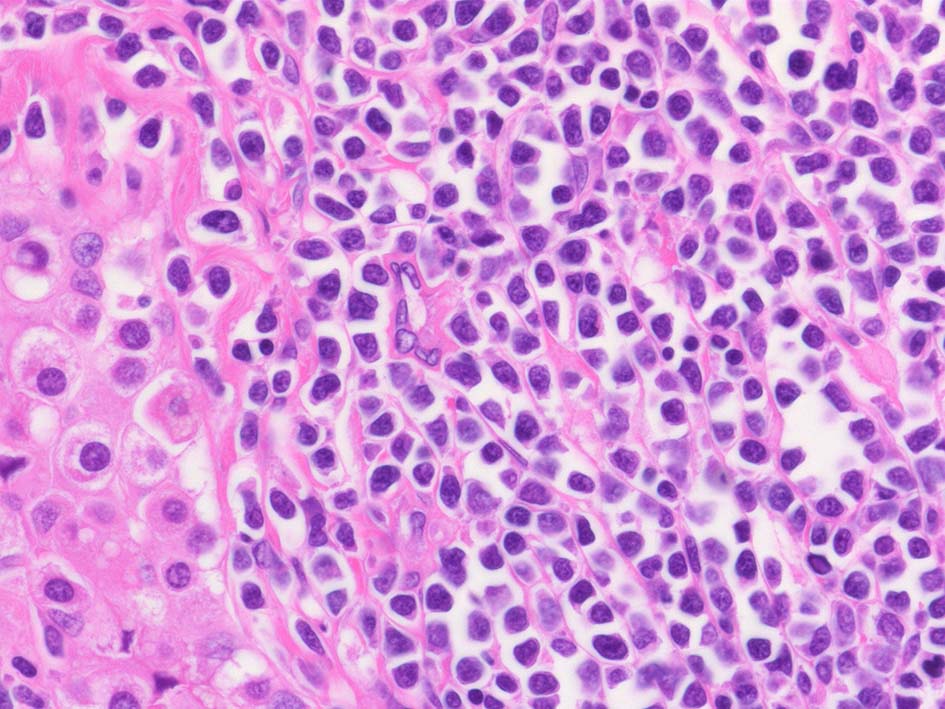

腫瘍内に壊死が認められる. 異型リンパ球の密な増殖により精細管は消失している.

腫瘍細胞はcentroblastic cells. mitosisやapoptosisが多い.